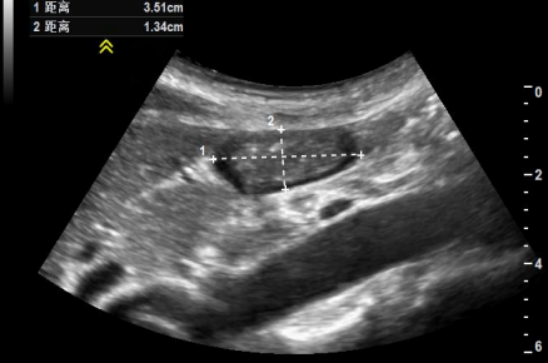

(1)双径法:CSA(cm2) =(前后径×头尾径×π)/ 4图9。

图片

图9  双径法(图中虚线1为头尾径, 虚线2为前后径)